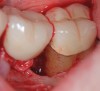

(10.) Intrasurgical photograph of treatment with mineralized FDBA and EMD.

Figure 10

The consensus report from the AAP's workshop group on intrabony defects presents evidence that periodontal regeneration in intrabony defects is possible on previously diseased root surfaces, demonstrated by gains in clinical attachments, reductions in periodontal pocket depths, gains in radiographic bone heights, and overall improvements in periodontal health.9 These clinical findings are consistent with available histologic evidence, and the clinical improvements can be maintained over long periods of time (ie, > 10 years).9 Although bone replacement grafts have been a commonly investigated modality, guided tissue regeneration, biologics, and combination therapies have also been shown to be effective. Early management offers the greatest potential for successful periodontal regeneration.9 Figure 9 through Figure 11 depict the treatment of a tooth with probing depths of equal to or greater than 15 mm using mineralized FDBA.

Regarding furcation defects, based on the available evidence, the AAP workshop concluded that regenerative therapy is a viable option to achieve predictable outcomes for their treatment in certain clinical scenarios.13 Periodontal regeneration has been established as a viable therapeutic option for the treatment of various furcation defects, including Class II defects, which represent a highly predictable scenario. The application of combined therapeutic approaches (ie, barrier, bone replacement graft with or without biologics) appears to offer an advantage over monotherapeutic algorithms.13 Figure 12 through Figure 15 depict the periodontal regenerative treatment of two previously restored teeth with intrabony and furcation defects using mineralized FDBA and EMD.